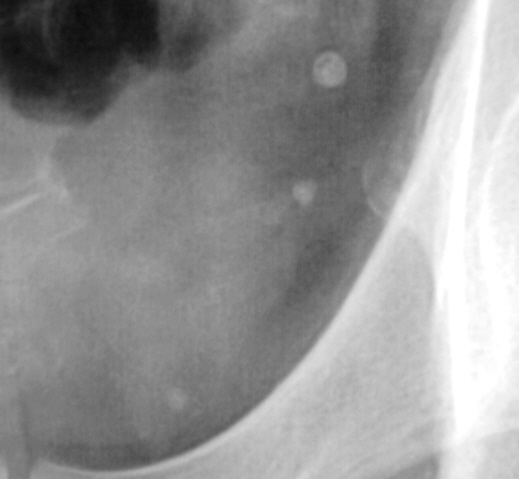

Иллюстрации 10, 11. 30 минута. Справа определяется эктазированная полая система (прегидронефротическая трансформация).

Вывод: Мочекаменная болезнь с локализацией конкрементов в полой системе левой почки и в нижней трети правого мочеточника. Эктазия полой системы правой почки.